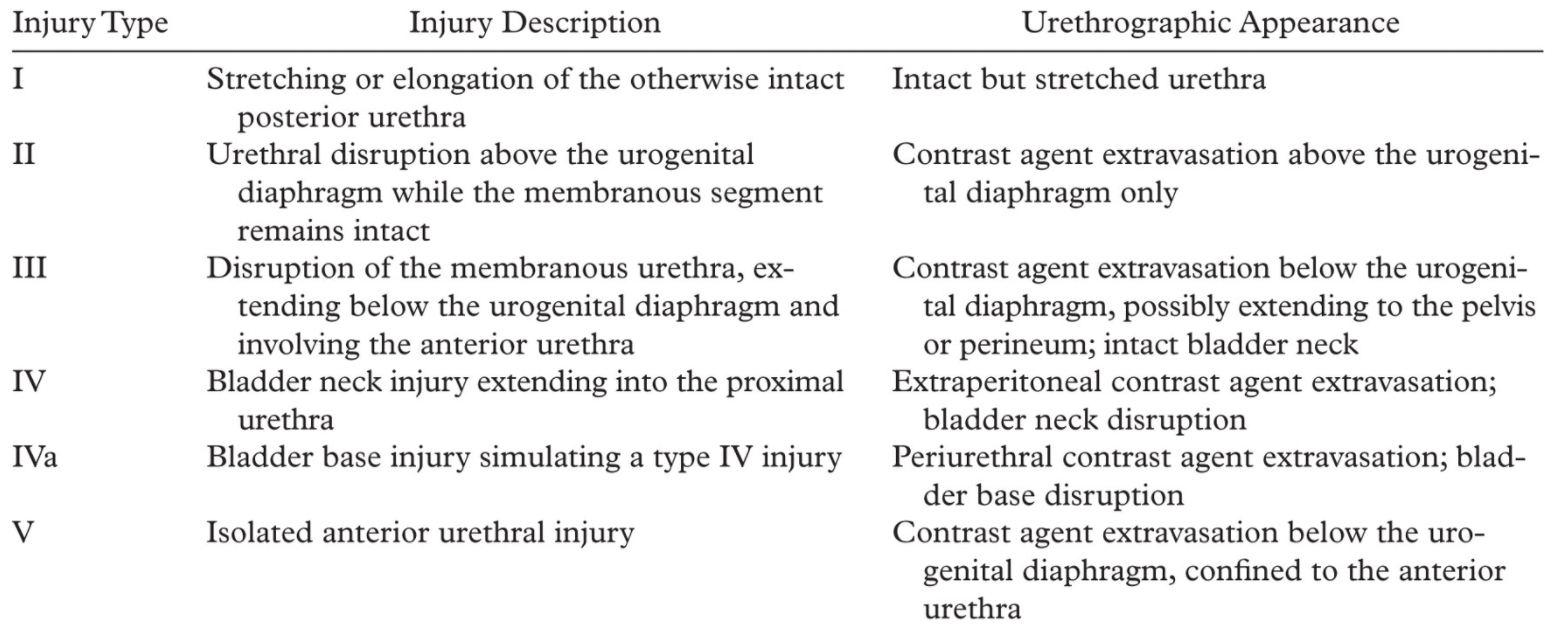

Classification de Goldman

Goldman I

Goldman II

Godlman III

Goldman IV

Goldman IVa